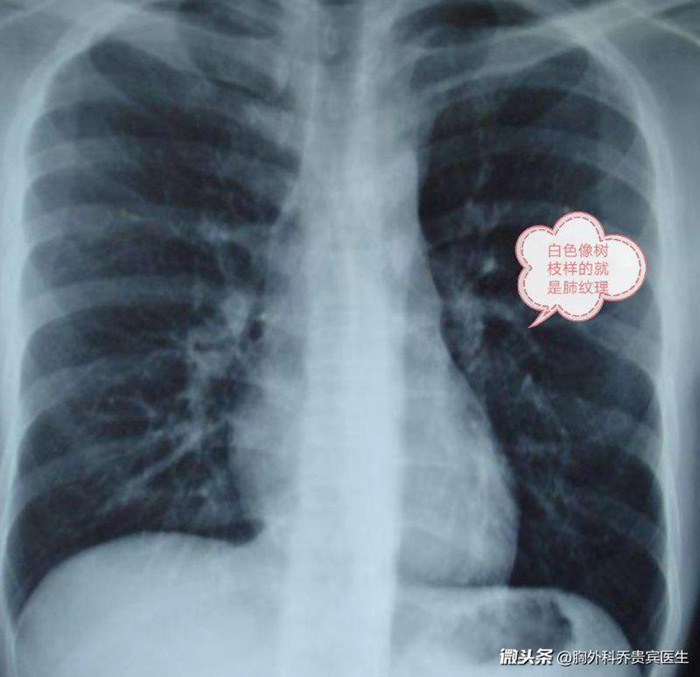

上述案例发出的时候,很多网友在评论里问“肺纹理增粗”“肺纹理增重”“肺纹理不清”是不是同样的意思?这2个词语也是在体检中经常出现的结论。其实,肺纹理是指胸片的胸部影像学检查时在影像学上出现的肺部条纹状的结构。

肺纹理常常是肺部的血管和细支气管的影子。肺纹理增重是一个影像学的名词。一般都是由于吸烟或者肺部感染,造成有细小的气管炎症或者血管有增粗增深的现象,出现时就会在影像学上表现为肺纹理增粗。往往没有临床症状或者器质性的疾病。所以, 同样不用担心。